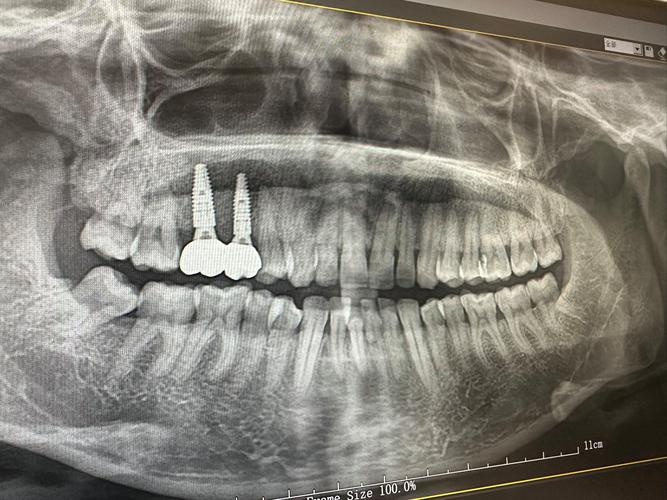

(图片来源网络,侵删)- 拍X光片:评估种植体周围骨高度、密度,以及是否有暗影(感染或吸收)。

- 临床检查:检查牙龈状态、种植体动度、咬合接触点。

- 牙周检查:测量牙周袋深度,判断是否有种植体周围炎。